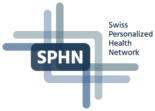

Phantom - Development

An anthropomorphic CT phantom has been developed. It highly realistically simulates the attenuation properties of human tissue. Figure 1 on the left shows the data set of an abdominal CT examination, and on the right, the corresponding CT measurements of the phantom. The red rectangle indicates the printable area (DIN A4). In the range of typical soft tissue HU values, there are hardly any visible differences between the phantom and a real patient examination. This is made possible by printing an iodine-containing ink on paper with an inkjet printer. The phantom can thus be built up layer by layer or in other words paper sheet by paper sheet. A previously acquired CT data set or artificially generated images can serve as a template.

Figure 1: Real patient examination (left) in comparison to phantom measurement (right).